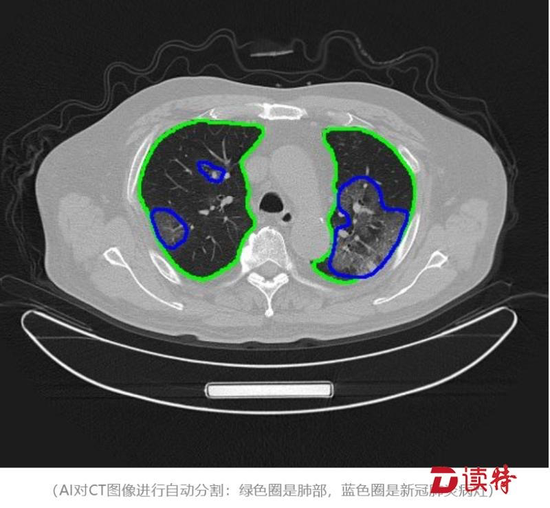

华大基因研制出病毒检测试剂盒,并第一时间捐赠湖北地区,5天内在武汉建成“火眼”实验室;12个小时,华为交付火神山医院首个“远程会诊平台”;36个小时,中建科工完成雷神山医院ICU病区室钢结构制造工程;1月24日至3月11日,顺丰全网合计运输超过1亿件包裹至湖北……

疫情伊始,云天励飞研发的人工智能红外测温设备及系统,可以快速识别发热患者,有效提高检测效率,在国务院联防联控机制新闻发布会上被点名表扬;腾讯用“腾讯觅影”AI辅助医生提高CT检查效率;普渡科技提供 “欢乐送”智能配送机器人,负责服务台问询、导诊、送餐等任务,甚至医院里高风险的消杀工作;大疆无人机协助交警开展执勤管控。